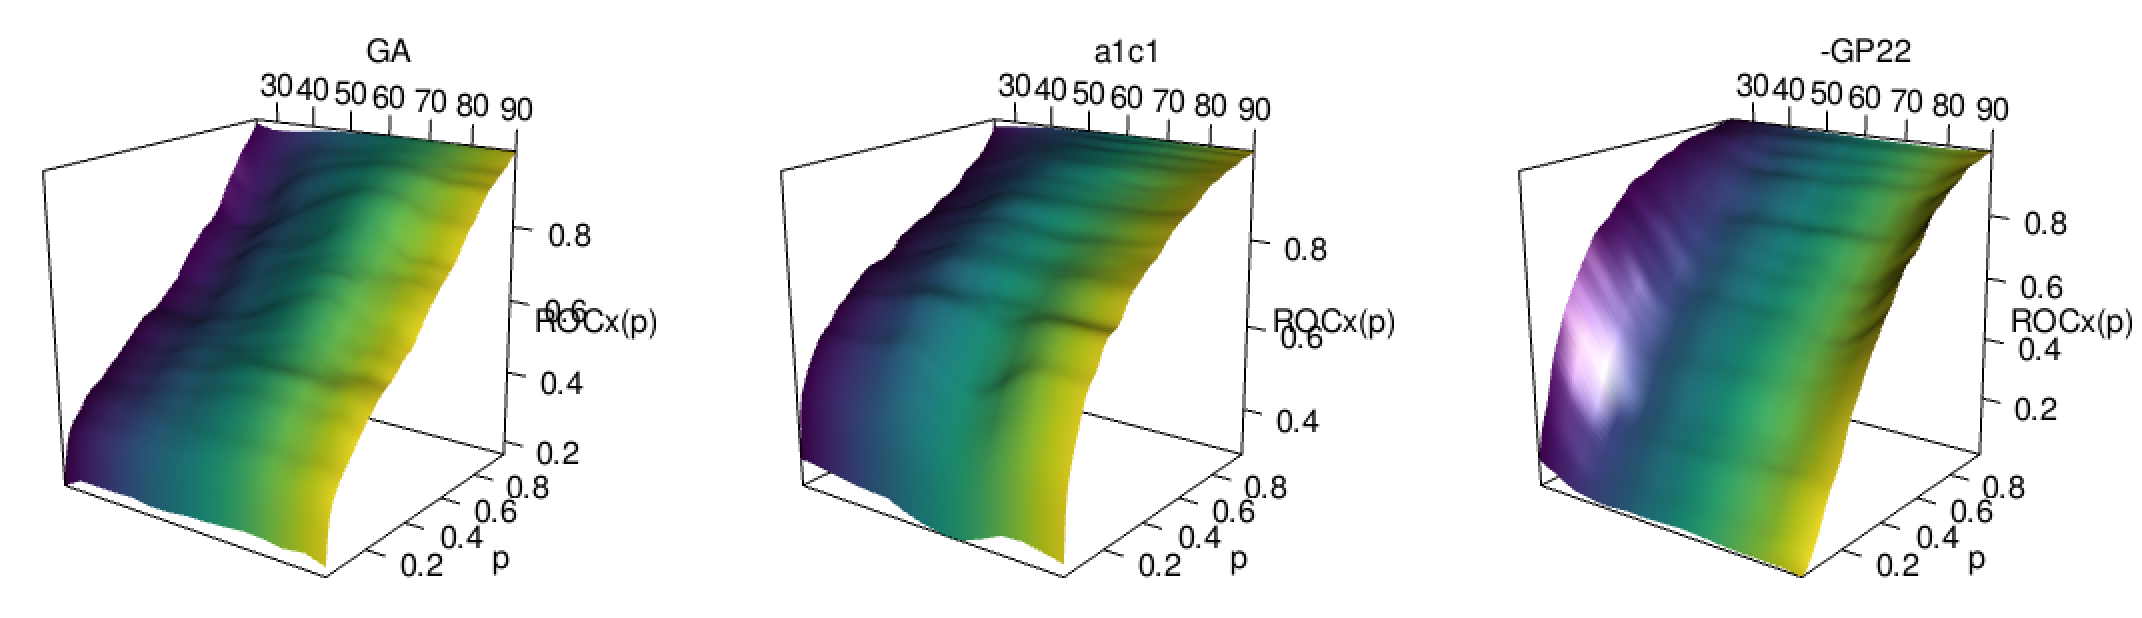

We begin our analysis by representing the conditional densities of the three diagnostic markers at certain ages, along with their corresponding conditional ROC curves. The resulting graphics are collected in Figure 4. Note that the third diagnostic variable appears now under the tab GP22. This is because, in this particular case, higher values of the diagnostic variables are more common in the healthy population, whereas the diseased subjects tend to have lower values, which goes against the assumptions made for the construction of a ROC curve. By taking the opposite values of this variable we ensure that the roles are exchanged.

At first sight it could appear that the conditional ROC curves remain constant through all those values, although we can appreciate a sort of hill for the medium age in the GA marker, and the GP22 seems to have better discriminatory power for the youngest patients, as the conditional ROC curves at those lower ages are closer to the point of maximum sensitivity and specificity.

However, there are two different issues that must be taken into consideration. First, the conditional ROC curve is estimated locally, which means that the estimations computed on the extreme values of the covariate are not as reliable, because they have fewer data around (and this condition exaggerates when the covariate is not uniformly distributed). Secondly, on those representations there is no insight on how the covariate is distributed in the healthy and in the diseased populations.

Next, we estimated the pooled and the covariate-adjusted ROC curves for each one of the diagnostic variables. We represented them in Figure 5. The conditional ROC curve was also estimated for certain values of the covariate, as well as their respective conditional area under the curve (AUC) with a pointwise 0.95 confidence interval (for more details of how to compute such confidence interval, check González-Manteiga et al.,, 2011). The summary measures AUC and area under the AROC curve (AAUC) were also estimated (they are represented as horizontal lines, as they do not depend on fixed values of the covariate).

Setting our attention on those summary measures and the pointwise confidence interval we can have a first insight of the relationship between the curves. For the considered confidence level, the AAUC falls inside the confidence interval for all the values of the covariate, for all the diagnostic markers. Of course, we have to take into account that it is not a confidence band, so the level should be adjusted, but in any case it seems that there may not be differences between those indices. The AUC and the AAUC, despite being presented without confidence intervals, seem to be very similar in the first two variables. The ROC and the AROC curves of GP22, however, are more separated (as their corresponding summary measures are).

Then, we perform a two-step study for each one of those diagnostic markers: first we test if the conditional ROC curve is constant for all the values of the covariate by comparing it with the AROC curve (using the test proposed in Rodríguez-Álvarez et al.,, 2011) and then we test whether the AROC and the ROC curves are equal (5) (using the test statistic described in 2, doing an even splitting of the sample for the dependency issues and considering 500 bootstrap iterations). The software R (R Core Team,, 2022) was used to run the analysis: the package npROCRegression (Rodríguez-Álvarez and Roca-Pardiñas,, 2023) was used for the first test, and the code implemented for the second test is provided the Appendix A. The obtained p-values, with their interpretation when we take a significance level of , are summarized in Table 4.

| GA | a1c1 | GP22 | ||||

|---|---|---|---|---|---|---|

| Test 1 | ||||||

| Test 2 | ||||||

| Use | Use | Use |

The conclusions that are drawn from that study match our previous suspicions: the covariate age does not seem to have a significant impact on the performance of each diagnostic marker. However, in the case of the GP22 marker we find differences between the ROC and the AROC curve, and thus the latter should be employed for further analysis of this diagnostic variable.